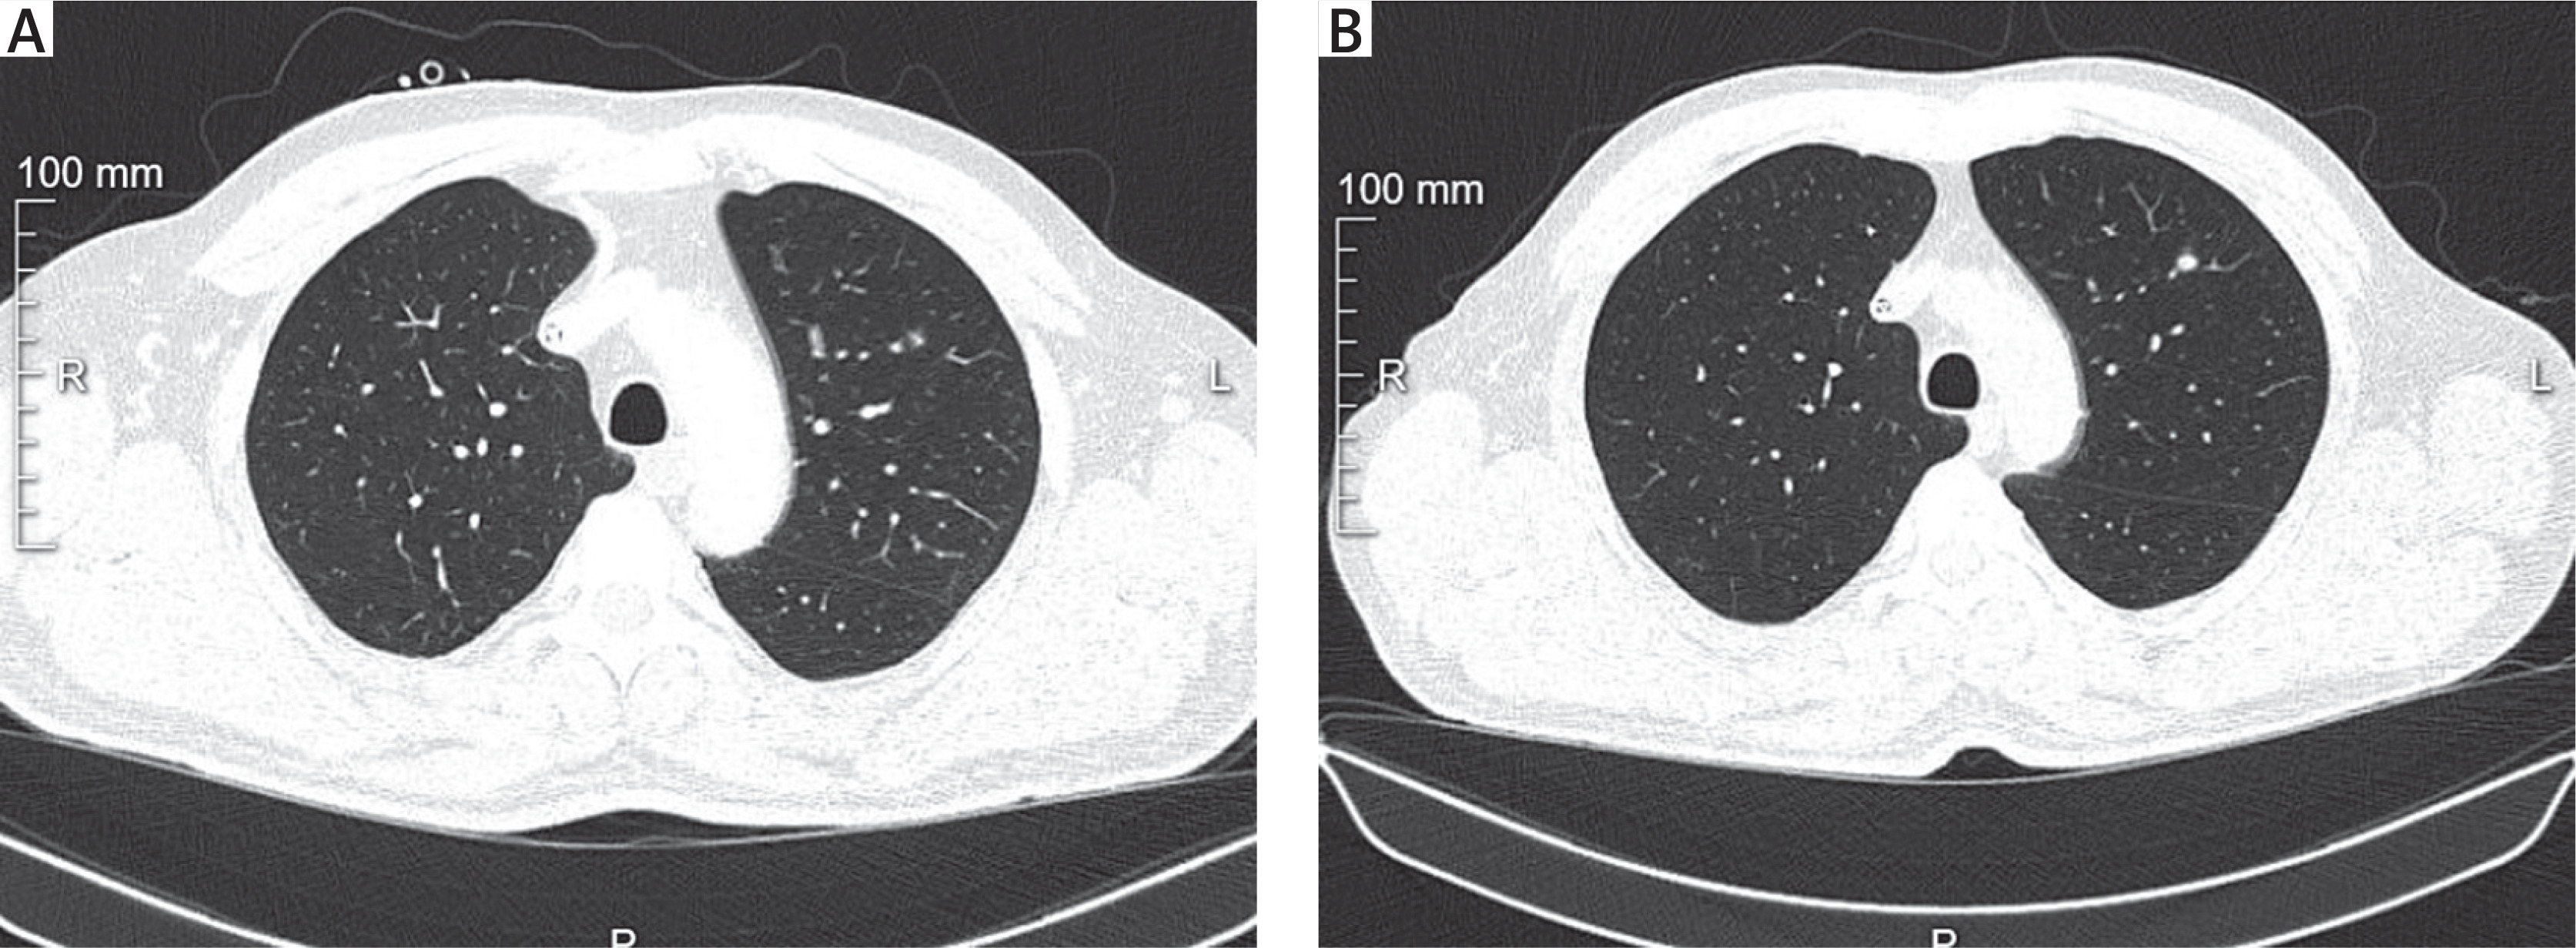

Surgical indication: Suspected pulmonary adenocarcinoma. Positron-emission tomography computed tomography (PET-CT) revealed a 5 mm nodule in the upper lobe of the left lung with SUV 1.3 (possibly underestimated due to respiratory motion). Preoperative CT showed a solid 5 mm nodule in segment 1 of the left lung with interval growth compared to 2023 CT (when the patient underwent gastrectomy for gastric cancer).

Lesion location: Segment S1+2 of the left lung; 5 mm diameter; deep parenchymal location; no enlarged lymph nodes on CT (Figure 1).